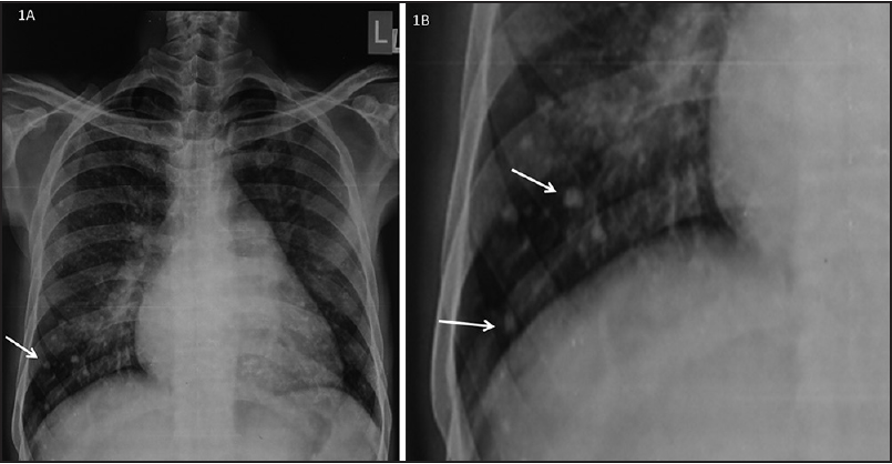

CXR Z

Left atrial enlargement

Elevation of left mainstem bronchus

Double contour of the right border of heart

PA view: ⇒ Left atrial enlargement:

- Double density of RTÂ cardiac border

- Elevation of the left main bronchus and splaying of the carina